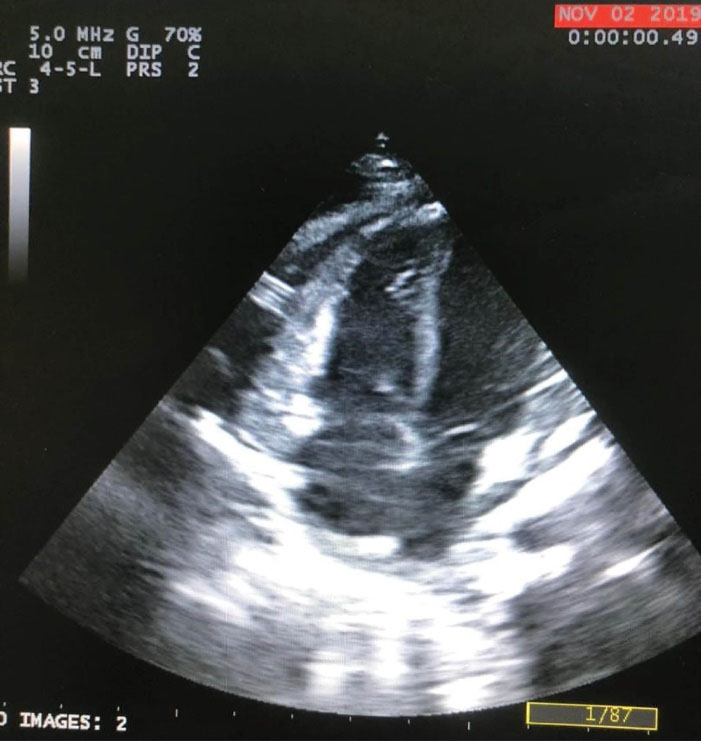

The patient planed for open-heart surgery and all the necessary arrangements were made.(). Cardiopulmonary bypass was conducted under general anesthesia with a middle sternotomy technique and cannulation of the superior and inferior vena cava. The body was cooled to 30 °C and the cardiopulmonary solution was injected from the root of the heart aorta. In the right ventricle, a vegetation of 5 cm long was observed originating from the entrance point of the VP shunt and continuing up to the right ventricular outflow tract and the tricuspid valve. The vegetation was extracted and the tip of the VP shunt was directed back to the peritoneal cavity. The tricuspid valve was intact with appropriate function. The right ventricle and atrium were repaired and the patient was detached from cardiopulmonary bypass after warming up. Two drains were placed in the pleural space and one drain in the mediastinum and the sternum was closed. The patient was transferred to the intensive care unit (ICU) in stable condition and recovered after one day. Two weeks later, the patient was discharged in stable condition. Two weeks after discharge, the patient presented again with symptoms of vomiting, tachypnea, and lethargy. Chest X-ray and thoracic echocardiography revealed that the VP shunt was again migrated about 2 cm into the anterior mediastinum ( and ). The patient underwent reoperation under general anesthesia and the VP shunt was shortened and re-inserted into the peritoneal cavity. The patient was transferred to the ICU in stable condition and recovered after 6 hours. Antibiotic treatment was continued for six weeks and the patient was discharged in stable condition. In follow-up visits after two years, the VP shunt functioned well and no particular complication was observed.

Figure 5. Echocardiography image: White arrow shows catheter tip.